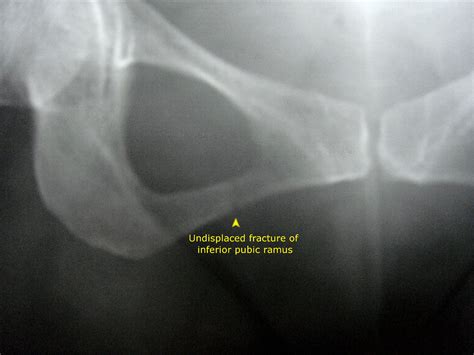

Diagnosing a Ramus Pubic Fracture involves a combination of physical examination and imaging tests. The diagnostic process typically includes:

• Physical Examination: A healthcare provider will assess the pelvic area for pain, swelling, and deformity.

• Imaging Tests: X-rays, CT scans, and MRI scans are commonly used to visualize the fracture and determine its extent.